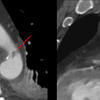

Min Aortic Injury

MAI x 2

Unusual location